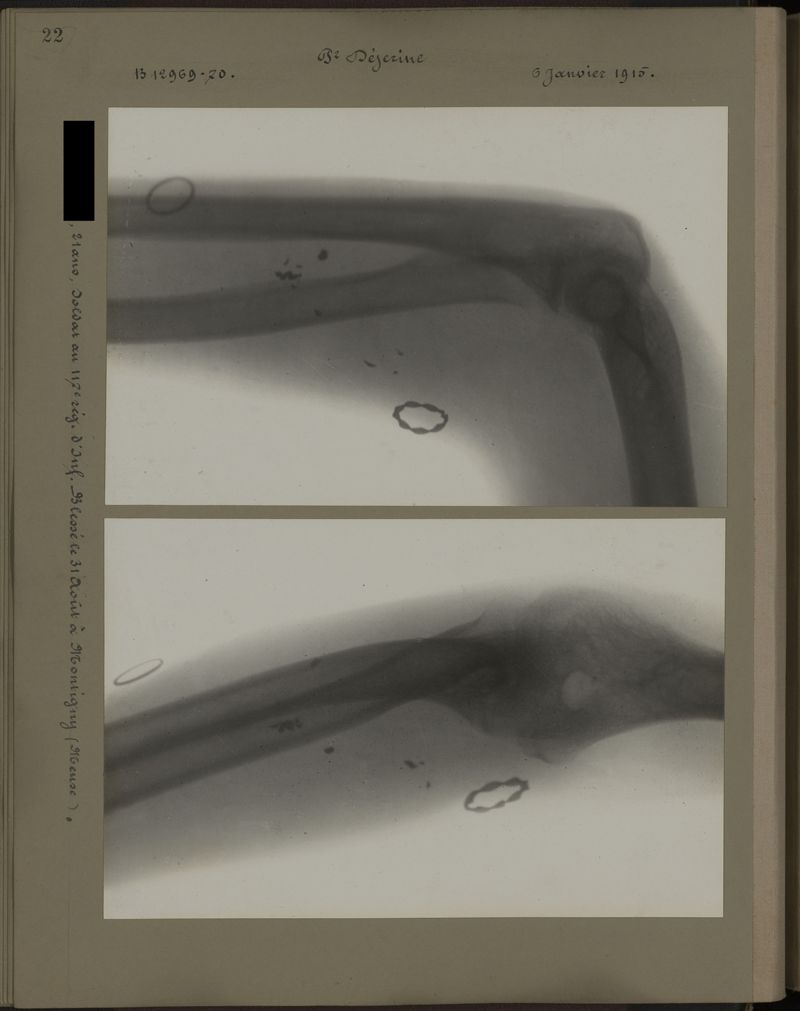

Deux albums de radiographies de la Première Guerre mondiale. Collection du laboratoire central de radiographie de la Salpêtrière. Deuxième album.

1915.